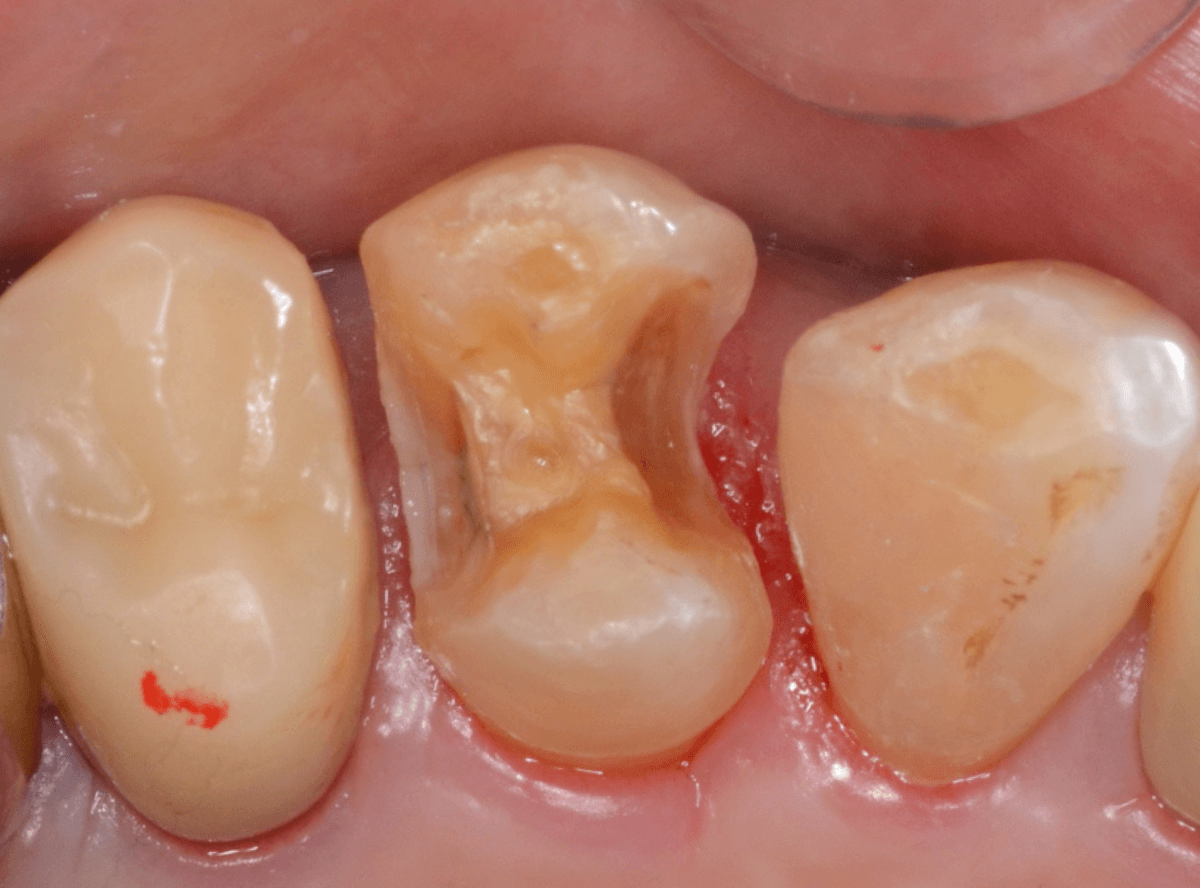

さし歯の土台の補修と、おやしらずの虫歯の処置をしたところです。

この状態で型をとります。

虫歯を全て除去しました。

幸い、あまり多く削る事なく進められたので良かったです。

手前の歯のつめ物も外します。

こちらもお薬が入っていますが、外して中を調べます。

こちらは中も問題なかったです。

奥歯は歯に優しいファイバー・コアで再製し、型取りします。